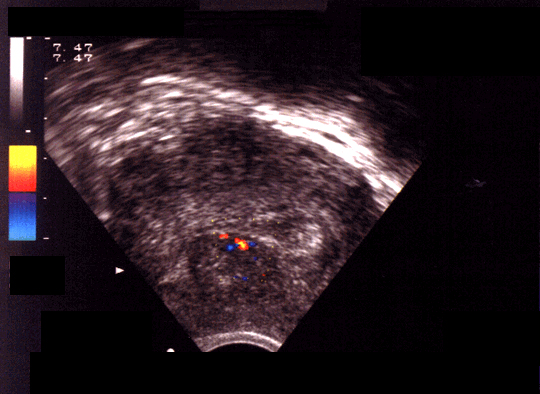

Myome sous-muqueux. On observe un déplacement de l'axe cavitaire, le doppler couleur identifie un vaisseau